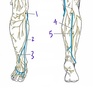

Which structure is labeled by #5?

Tibial nerve

Which structure is labeled by #1?

Tibia

Which nerve supplies the areas indicated in yellow (#2 and #2a)?

2a is supplied by the saphenous nerve, a branch of the femoral nerve

Femoral nerve

Which structure is labeled by #3?

Femoral artery and femoral vein

Fig. 59.7 Adapted from Gilroy et al. Atlas of Anatomy, second edition, Fig. 29.34 B.

Identify the structures of the lateral compartment of the leg.

What innervates them?

Fibularis longus (5)

Fibularis brevis (6)

Superficial fibular nerve